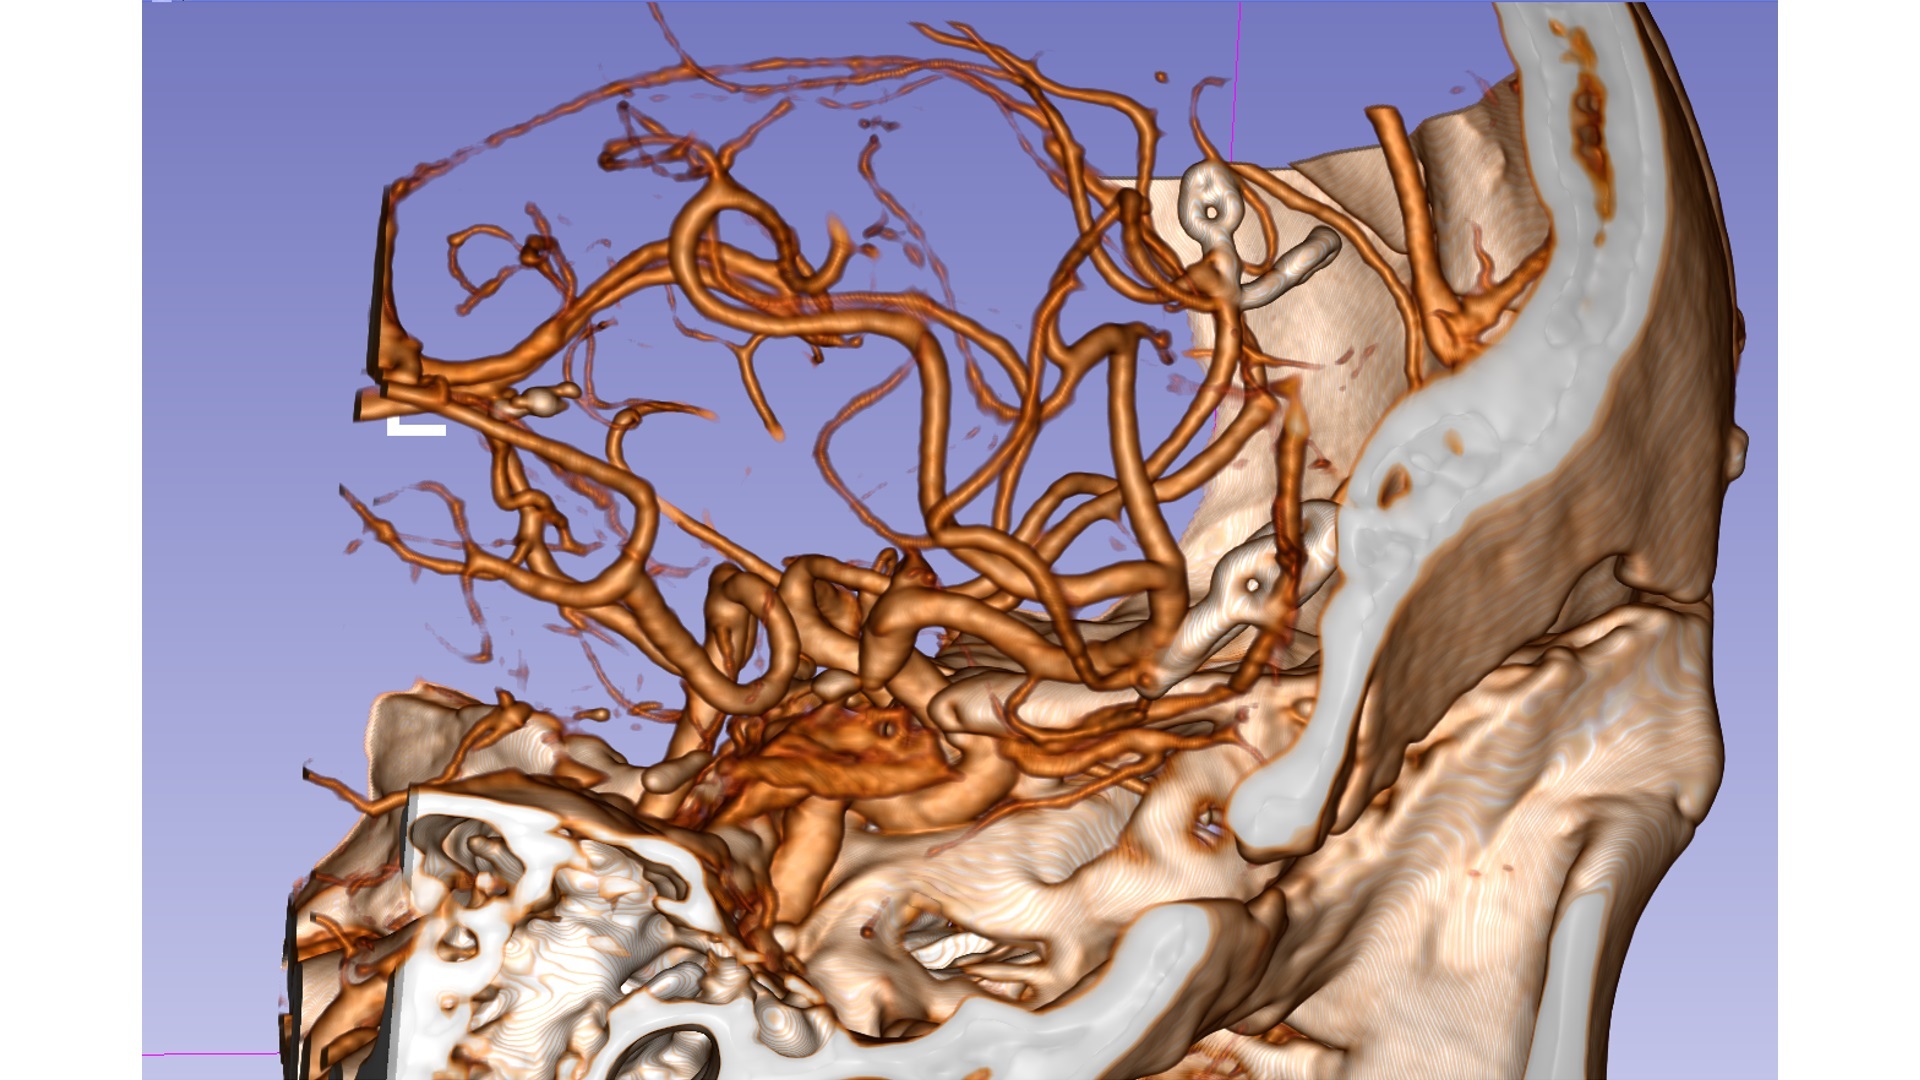

造影显示颅内多发动脉瘤:右侧大脑中动脉瘤;右侧A2-A3交界处动脉瘤;右侧后交通可疑动脉瘤。

右侧大脑中动脉瘤位于分叉部。

右侧A2/A3动脉瘤近端有一分支血管。

然后前纵裂入路,显露A2、A3动脉瘤,动脉瘤顶嵌入脑组织。

如图所示:显露动脉瘤及载瘤动脉及分支的关系

为保留动脉瘤近端分支血管,多次调整动脉瘤夹,最终两枚动脉瘤夹夹闭完全,载瘤血管通畅。